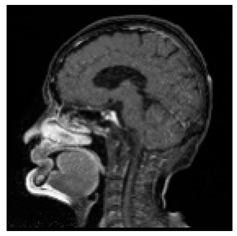

| Original Medical Images | |||||||

| Pair 1 | Pair 2 | Pair 3 | Pair 4 | ||||

![]() (1-9) PSNR = 44.14 | ![]() (1-10) PSNR = 41.90 | ![]() (1-11) PSNR = 40.09 | ![]() (1-12) PSNR = 41.41 | ![]() (1-13) PSNR = 42.24 | ![]() (1-14) PSNR = 40.35 | ![]() (1-15) PSNR = 40.79 | ![]() (1-16) PSNR = 40.84 |

| Shadow Images Produced by Using LSBs | |||||||

![]() (1-17) PSNR = 26.35 | ![]() (1-18) PSNR = 25.49 | ![]() (1-19) PSNR = 23.57 | ![]() (1-20) PSNR = 24.19 | ![]() (1-21) PSNR = 24.79 | ![]() (1-22) PSNR = 24.23 | ![]() (1-23) PSNR = 23.26 | ![]() (1-24) PSNR = 24.42 |

| Shadow Images Produced by Using Middle Bits | |||||||

![]() (1-25) PSNR = 18.97 | ![]() (1-26) PSNR = 19.95 | ![]() (1-27) PSNR = 14.10 | ![]() (1-28) PSNR = 13.84 | ![]() (1-29) PSNR = 16.66 | ![]() (1-30) PSNR = 13.23 | ![]() (1-31) PSNR = 13.38 | ![]() (1-32) PSNR = 14.75 |

| Shadow Images Produced by Using MSBs | |||||||